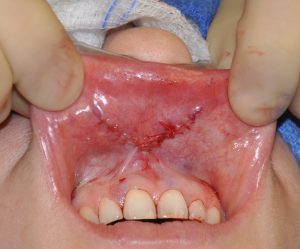

Unlike traditional lip lifts that shorten the distance between the nose and lip, V-Y primarily increases lip volume and visible “pink” vermilion show without external scarring because all incisions are inside the mouth.

This young female had lost volume in the center of the lower lip from a prior bony genioplasty procedure. She desired more central lower lip fullness.

- No visible external scars (incisions are inside the mouth).